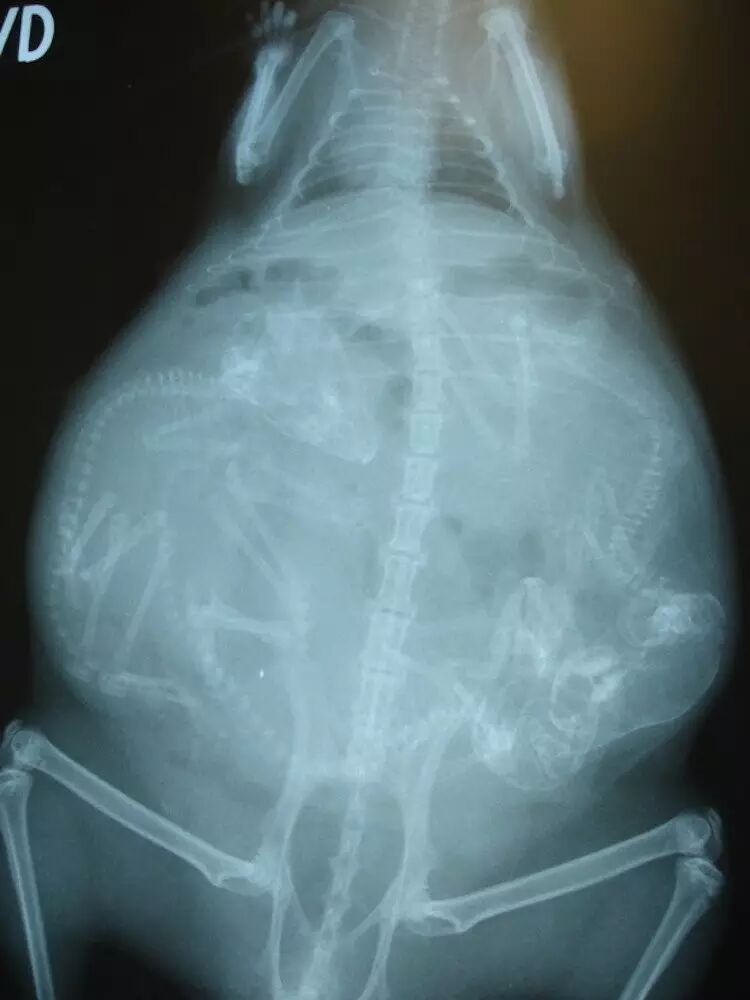

怀孕是一个非常神奇的生物现象,而这些X 光照片就更加证明到生命的奇迹让人百看不厌,从我们熟悉的猫和狗到较少见的龟、蝙蝠影像也有,大家可以看看以下,并比对和人相比的差异与相同之处。

怀孕的天竺鼠。